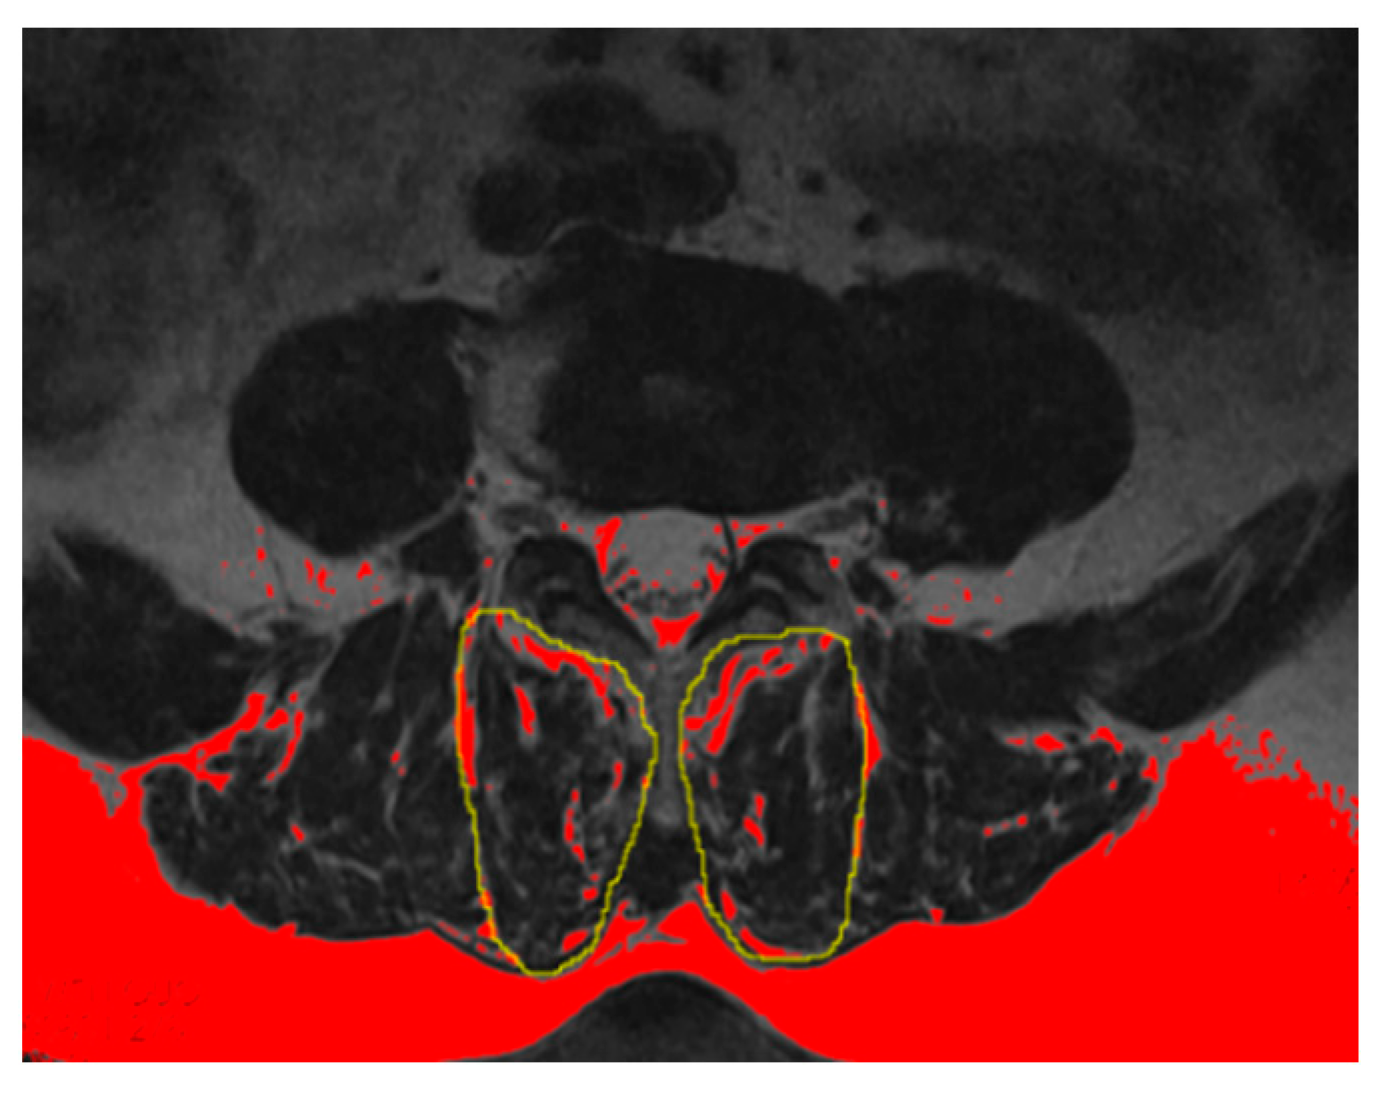

The multifidus muscle (MM) has been the most studied and commonly used measurement with which to evaluate the fat infiltration and atrophy of PVM [11,12]. The percentage of the fat infiltration area (%FIA) was measured via axial T2-weighed imaging at the L4-L5 disc level by using ImageJ software (Version 2.0.0, National Institutes of Health, Bethesda, MD, USA). First, we converted each image into a grayscale 8-bit image. We then outlined the region of the multifidus muscle using the threshold technique and utilized a “default” and “dark background” method to obtain the value of the threshold automatically. Last, we calculated the %FIA; the red area in the 8-bit image was the fat tissue, and the fat tissue divided by the region of the multifidus muscle was the %FIA (Figure 4) [13].

Figure 4.

Example of fat tissue (red color) of the MM showed in the ImageJ software (Version 2.0.0, National Institutes of Health, Bethesda, MD, USA).